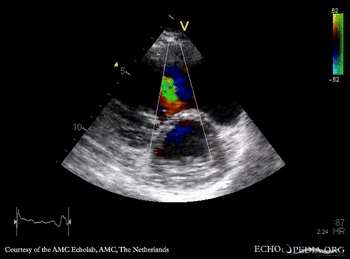

TEE: muscular VSD